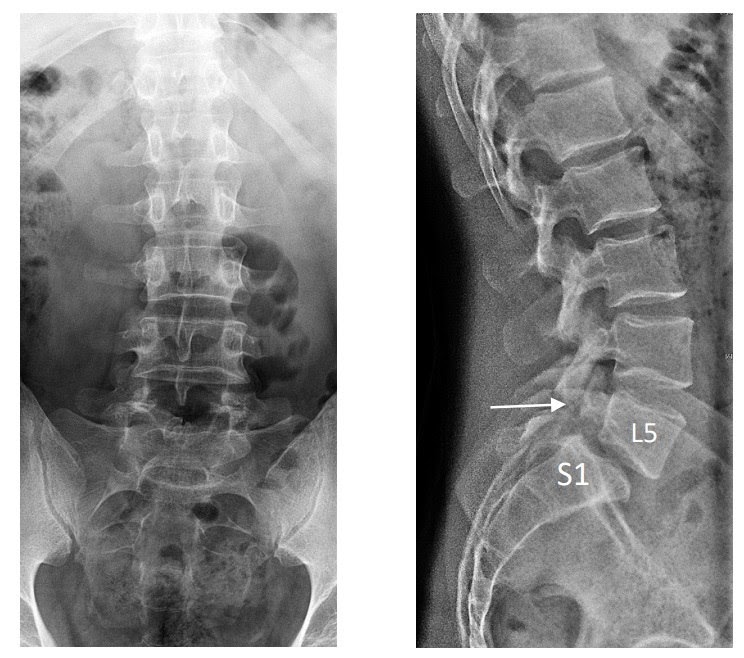

🔎На снимках видны дефект межсуставного отдела дужки L5 позвонка (стрелка) и смещение тела L5 (пятый поясничный позвонок) вперед до 1/4 по отношению к нижележащему позвонку (S1- первый крестцовый позвонок).

Диагноз:

• Спондилолиз — дефект межсуставного отдела дужки позвонка.

• Спондилолистез I степень (по Meyerding) — смещение вышележащего позвонка вперед по отношению к нижележащему позвонку.